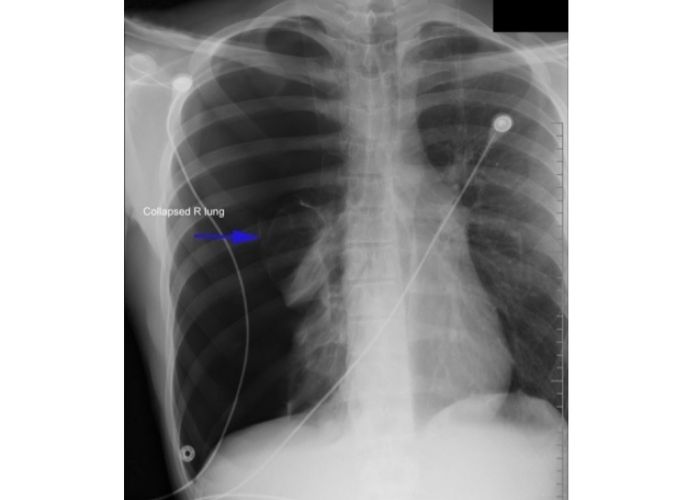

PNÖMOTORAKS

Pnömotoraks Nedir?

Göğüs boşluğu içinde akciğer zarları arasında hava toplanması ve akciğerin sönmesidir.Hastalarda ani başlayan nefes darlığı ve göğüs ağrısı ,çarpıntı, öksürük ve nadiren dudaklarda morarma olabilir.

Pnömotoraks Tanısı Nasıl Konulur?

Öncelikle hızlı tanı konması hayati tehlike taşıdığından önem arz eder. Hastanın semptomları, fizik muayene bulguları ve radyolojik görüntüsü ile tanı konulur. Şüphe duyulduğunda BT çekilebilir.